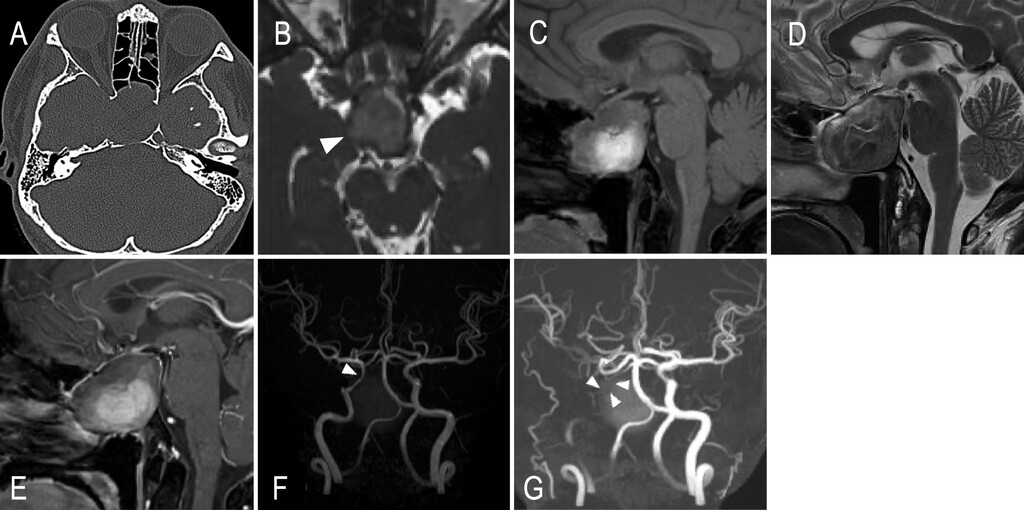

● CT检查可见蝶窦占位,右侧海绵窦、鞍底及斜坡存在溶骨性改变(图1A);MRI检查见一直径39毫米的肿物充满蝶窦,与鞍底边界不清,稳态构成干扰序列显示病变向右侧动眼神经池延伸(图1B),并将正常垂体向上推移,病变信号不均,呈高信号与等信号混杂(图1C、D),提示出血或富含蛋白成分,无强化表现(图1E);MR血管成像显示右侧颈内动脉轻度狭窄(图1F),弥散加权成像未见缺血灶。尽管患者无相关缺血症状,但4天后复查MR血管成像显示狭窄显著加重,近乎闭塞(图1G),CT灌注血管成像证实右侧颈内动脉重度狭窄(图2A),尽管右侧颈内动脉存在狭窄,但右侧大脑中动脉供血区脑血流量、脑血容量未下降,然而平均通过时间与达峰时间延长,提示广泛灌注延迟(图2B)。除视神经、动眼神经症状快速进展外,患者还出现颈内动脉急性近乎闭塞伴脑灌注不足,因此紧急实施手术干预。

图1:A:CT示右侧海绵窦、鞍底及斜坡溶骨性改变。B:入院时CISS MR图像,示右侧动眼神经受囊肿压迫(箭头尖)。C-E:入院时T1加权像(C)、T2加权像(D)、钆增强T1加权像(E)。F:入院时MR血管造影,示C3段轻度狭窄(箭头尖)。G:入院后4天MR血管造影,示右侧颈内动脉近乎闭塞(箭头尖),右侧大脑中动脉显影变淡。